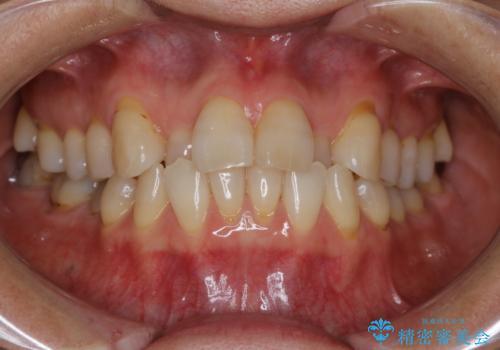

前歯の反対咬合、奥に引っ込んでしまっている歯をインビザラインで治療する

骨格性の受け口の矯正 部分ワイヤーで上の前歯を前に、 マウスピースで下の前歯を後ろに。

補助装置を用いて奥歯の咬み合わせを事前に改善 インビザラインによる矯正治療

引っ込んだ前歯を並べたい マウスピースと部分ワイヤーのコンビネーション矯正

【インビザライン】前歯のがたつきを目立たない装置で治療